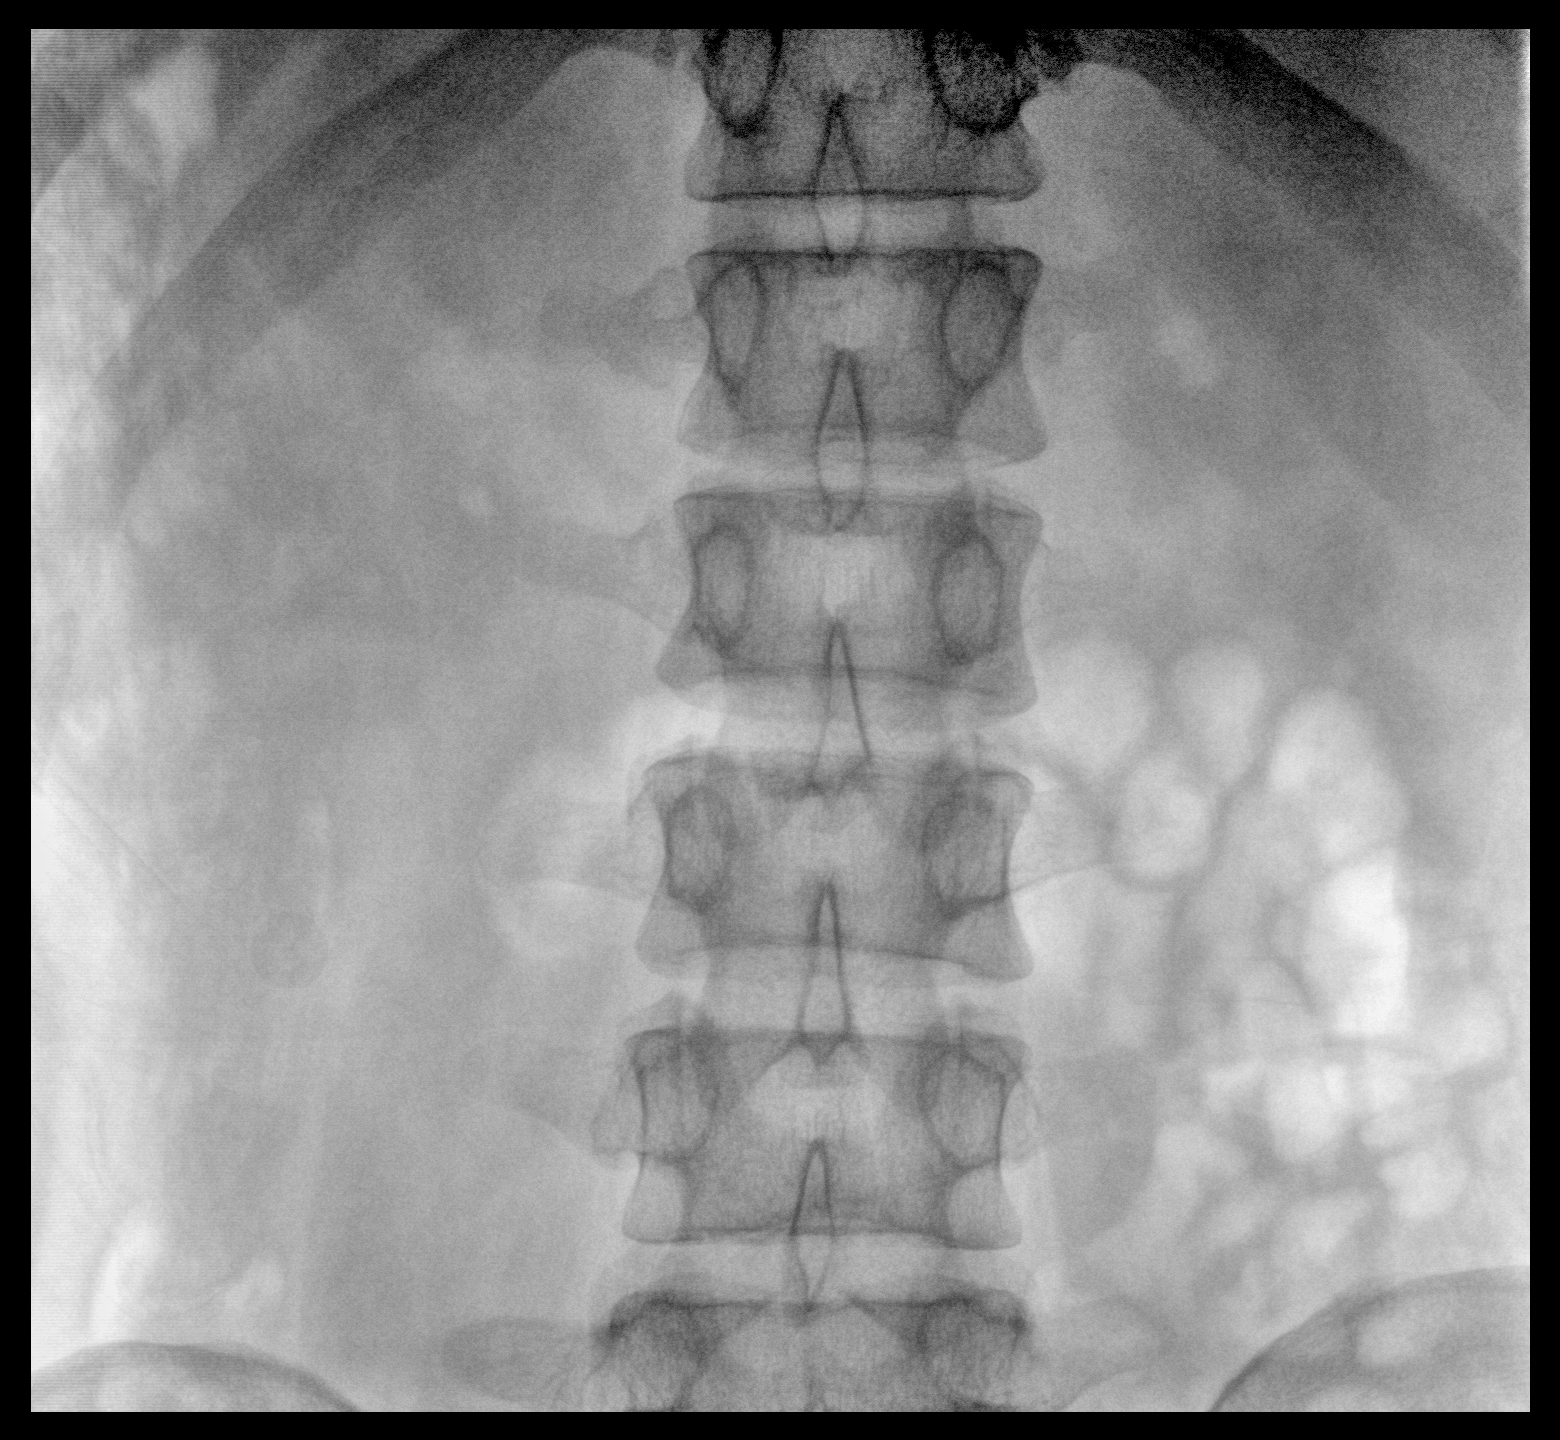

PLX118F-Plus配备了两种平板尺寸,大尺寸动态平板探测器成像面积较传统平板探测器提升了25%以上,在视野需求大的手术中,便于医生更好定位病灶点,规划手术方案,减少因视野范围不足而多次透视、点片造成的不便,不仅提高了手术效率,也减少了辐射剂量。